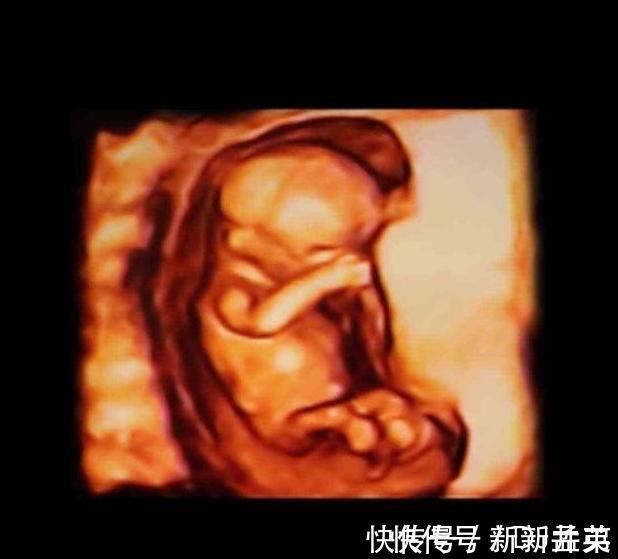

13-15周,胎儿的眼睛开始转动,大脑也在飞速地发育,胎儿的小脸已经和成人差不多了,神经元开始增多,条件反射也开始增加,胎儿身材比例越来越合理了。